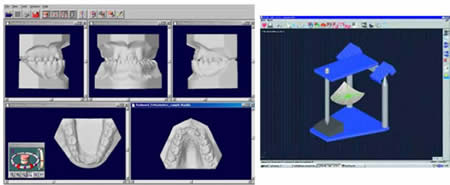

Introducción.- En oclusión, existen varios campos de aplicación básica para la digitalización. Hablamos, preferentemente, de la digitali- zación tridimensional. Recordemos que esta palabra es sinónimo de medición y –como tal- auxilio en esta rama odontológica tan necesitada de precisión. La digitalización tridimensional consistirá en el registro de la posición espacial, de un finito número de puntos, determinando sus coordenadas -x,y,z-. A menor distancia entre cada punto se conseguirá como resultado un objeto virtual con mayor detalle, coincidente con el real. Con cada triada se podrá formar una superficie, que continuada con la generada por el resto de la malla de puntos, completarán la forma del objeto. Este es el origen de donde partimos para establecer el concepto básico de las revolucionarias aplicaciones 3D. Se parte así del denominado escaneado tridimensional: Escaneado Superficial de un objeto real -> “Nube de Puntos” -> “Malla de Alambre” -> Superficie del Objeto Virtual. Con los modelos dentarios, impresiones o registros de oclusión, virtuales (en la pantalla del ordenador), realizaremos ahora, mediante un programa informático, la manipulación simulada, mediante computadora, para la realización del estudio y diseño de la oclusión. La Oclusión Computarizada (OC) –dentro de la más amplia Odontología Computarizada- comprende, hoy, fundamentalmente, tres fines: 1º)- El Estudio, Diagnóstico y Plan de Tratamiento Asistidos por Ordenador. 2º)- El Encerado Computarizado. (Por RP –Rapid Prototyping-, Prototipado Rápido, o por CAM –Computer Assisted or Aided Machining or Manufacturing-, Maquinado Asistido o Ayudado por Computador). 3º)- La Restauración y Confección de Prótesis Computarizada. (Por CAD-CAM, -Computer Assisted Design – Computer Assisted Manufacturing-, Diseño y Fabricación Asistidas por Computador). La Odontología Computarizada tiene entre sus numerosas secciones, ésta de oclusión, considerada primordial en el trabajo clínico habitual, desde la que nos relacionamos con la ortodoncia, cirugía implantológica, tecnología protésica y prostodoncia. Cada uno de los citados fines de la OC necesita partir de un escaneado tridimensional de los objetos a tratar: elementos del sistema dentario (arcadas) –de forma directa, en la misma boca del paciente-, o modelos dentales obtenidos por una impresión material de éstas y su posterior escaneado –o forma indirecta, fuera de la boca del paciente-. El escaneado se puede realizar con variados dispositivos, resultando procedimientos de distintos tipos y con diferentes características, clasificados simplificadamente como: A) Escaneado de contacto, háptico: B) Escaneado sin contacto: Tomando una imagen del objeto, marcado por líneas o cuadrículas luminosas proyectadas sobre su superficie, que se deforman con ella, analizándose luego digitalmente. El escaner se considera aquí un analizador trigonométrico del objeto, que registra su imagen, marcada mediante un rayado por luz –normalmente láser- (que permite, mediante software, obtener las coordenadas espaciales de multitud de puntos, que son agrupados en unidades de tres, constituyendo los vértices de una superficie triangular, que sumándose a las vecinas, llegarán a representar la envuelta completa del objeto y así su forma volumétrica o tridimensional). C) Combinado. Externo e Interno. Los escáneres suelen resultar, actualmente, poco económicos, y aunque van decreciendo en coste, están –para estas fechas- en un nivel que suele partir como mínimo de los 8.000 euros; siempre dependiendo del procedimiento de registro empleado, tamaño y precisión del escaneado. Existen: A) aparatos integrados en sistemas dentales, desarrollados específicamente para nuestro campo, de comprobada eficacia y de alto coste económico; B) dispositivos de uso general, aplicables a los propósitos de la odontología, de complicada adaptación pero de muy bajo coste relativo; C) múltiples posibilidades para la construcción de un escaner propio, casero y económico, que pueda, con suficiente experiencia, llegar a funcionar para uso profesional, gracias a la existencia de suficiente información de la tecnología empleada, ampliamente divulgada y de fácil desarrollo; útiles para fines diagnósticos. En oclusión necesitamos el 3D, pero también el 4D. Sumamos aquí a las tres coordenadas espaciales de cada punto del objeto, otra más, la cuarta dimensión: el tiempo. Dado que un objeto móvil, lo es por la temporalidad de sus posiciones en el espacio. Así se registrarán y analizarán digitalmente los movimientos mandibulares para conseguir la articulación y reproducción de la función masticatoria. Para esto se han aplicado determinados registros, mediante sensores de posición o por receptores de actividad muscular, como los electromiógrafos, o el más específico articulador virtual, del que se encuentran diferentes productos de software, englobados –como complemento necesario- en los programas que acompañan a los distintos sistemas de cad-cam dental. Desde el escaneado, o transformación u obtención del objeto real en cuerpo 3D, numérico, adquirido para ser estudiado y manipulado de forma digital, virtual, en el computador, continuamos con otras vías, ahora posibles, de enorme potencial, desde el estudio y planificación a la fabricación protésica. Así van a ser expuestas a continuación: A) La planificación; B) el encerado; y C) la fabricación. A) -Estudio, Diagnóstico y Plan de Tratamiento Asistidos por Ordenador. La planificación de la rehabilitación oclusal, puede iniciarse: A-1) Por Registro Estático Morfológico Computarizado, del aparato estomatognático y sistema dentario. Que puede realizarse: I) A partir de Escaneado Extraoral. I-a) Escaneado Volumétrico (CT–tomografía computarizada-) (O mejor, CBCT –tomografía computarizada de haz cónico-, de menor radiación y coste, con aparatos diseñados específicamente para uso dento-máxilo-facial ). I-b) Escaneado Superficial –de los modelos de estudio- y Registros Oclusales-. II) A partir de Escaneado Intraoral. II-a) Escaneado Volumétrico (CT local, o CBCT local, que se están desarrollando para aplicación retroalveolar). II-b) Escaneado Superficial –de las caras oclusales del sistema dentario-. A-2) Por Registro (Estático Morfológico Computarizado) de Huellas de Oclusión (o Registros Oclusales), para análisis de contactos intermaxilares, estáticos -y menos o indirectamente los movimientos mandibulares-. Mediante escaneado superficial de registros, sus modelos 3D, y combinación o no, con el Papel de Articular Electrónico (T-Scan). A-3) Por Registro Dinámico Funcional (fisiológico) Computarizado: I) Registro Computarizado (Integrado) de los Movimientos Mandibulares –electropantográfico o cinematográfico-. Por sensores o marcadores de posición. II) Registro Computarizado (Integrado) de la Función Muscular –electromiográfico-. A-4) Por Integración Informática de varios de los Registros citados. B) -Encerado Computarizado. Es el modelado o diseño virtual en la pantalla del ordenador y su realización en material de patronaje (como la cera u otro de similar; económico, modificable, transformable y rápido), que puede realizarse por: B-1) Por RP –prototipado aditivo- o B-2) por CAM –maquinado sustractivo-. Como pensamos en el concepto clásico, la realización de un encerado diagnóstico es clave para una rehabilitación oclusal correcta. Además el encerado servirá para la confección de: a) una posible férula radiológica y quirúrgica, b) una referencia para el tallado, la prótesis o rehabilitación temporal y el patrón para la definitiva. Se llevará a cabo, en dos etapas: 1ª) Etapa de creación del patrón. Elaboración virtual en la pantalla del ordenador. Necesitando el software apropiado, CAD. 2ª) Etapa de confección. Elaboración Real, mediante RP o CAM. 1ª) La etapa de creación virtual del patrón en la pantalla del ordenador, mediante un programa informático de diseño y manejo de objetos tridimensionales, (siempre partiendo de un registro previo, como el escaneado de los modelos), puede facilitarse con varias herramientas para: -Elaboración Virtual por Adición. 2ª) La etapa de confección, o elaboración real, mediante RP o CAM. -Confección por RP (Rapid Prototyping) –Prototipado Rápido-, de adición o construcción capa a capa, añadiendo una sustancia que se endurece, aumentando su nivel en superficie. La elaboración real por adición, es posible en un variado –pero limitado- tipo de materiales. -Confección por CAM (Computer Aided Machining) –Maquinado o Tallado Asistido por Ordenador-, de eliminación de sustancia o esculpido en un bloque sólido. La elaboración real por sustracción, es posible en un numeroso -y casi ilimitado- tipo de materiales. Existen gran cantidad de dispositivos que consiguen la fabricación y consecución física de un encerado real, a partir de su elaboración virtual, desde un escaneado y su diseño computarizado. Todos los sistemas denominados de cad-cam dental, en general, aunque no estén espe- cialmente dispuestos para ello, pueden dedicarse a este propósito; simplemente colocando un material de patronaje, como la cera, en lugar del material con el que se constituirá la prótesis definitiva. Pero, existen –también- sistemas espe- cialmente configurados para el trabajo en material de diseño, normalmente: ceras, resinas o compuestos, es lo que se denomina prototipado rápido (rapid prototyping). En la industria general, la fabricación de cualquier objeto en serie, requiere de estos procedimientos en las primeras etapas de elaboración para su producción. La más económica y reducida Impresora 3D o Sistema de Prototipado Rápido, que puede confeccionarnos unos maxilares, a partir de la tomografía, o un encerado diagnóstico, según el software disponible. Su precio actual 45.000 Euros. C) -Restauración y Confección de Prótesis Computarizada. (Por CAD-CAM). Es el modelado o diseño virtual en la pantalla del ordenador y su realización en material definitivo (como porcelana, titanio, aleación preciosa, u otro similar); poco económico, difícilmente o no modificable, ni transformable y que requiere de un tiempo adecuado, mucho mayor que el requerido para la confección del patrón de material plástico. Esto puede realizarse por numerosos dispositivos. Existen gran variedad de sistemas para el diseño y confección de restauraciones y prótesis. Son los denominados gene- ralmente SISTEMAS DE CAD-CAM DEN- TAL (Dental Cad-Cam System): (Entre estos sistemas encontramos los que también pueden planificar el tratamiento restaurativo y realizar el encerado diagnóstico con diseño y confección de un patrón oclusal; como hemos referido antes). Históricamente estos sistemas comenzaron con la década de los setenta -en 1971, con el Holodontography-Altschuler System-, y con el Sopha System de Duret, progresando enormemente hasta comienzos de los noventa. Durante esos veinte años, se potenció su desarrollo con el siguiente hito histórico que los encumbró, en su segunda década, por la aparición de los principales impulsores del cad-cam clínico comercializable -Mörmann y Brandestini, en 1981-, denominado Sistema Cerec. También se establecieron los principios de estos dispositivos con el DCS Dental System, el CAP System, el Minnesota-Rekow System, el Nissan Cad/Cam System, Automill y Microdenta System. El culmen del progreso se alcanzó a mediados de los noventa, con sistemas ampliamente comercializados y evolucionados hasta hoy: Procera, DCS Dental, o Cicero. En los siguientes diez años, se continuó perfeccionando los sistemas citados; hubo algunos sistemas no comerciales o de escasa difusión, o distribuidos moderadamente; repre- sentando un período hasta el 2000, con una pequeña depresión, en los años medios, por el declive en la extensión de estos productos, en relación al extraordinario futuro que se les auguraba, motivada por el alto coste de los equipos y las limitaciones en su potencia digital, en el que –aún y así- aparecieron sistemas como: Belledent, Cadim, Dentscan, CCD System, Cynovad, Digident-Girrbach, Decim y Etkon. La segunda revolución para la odontología por cad-cam se produjo con el comienzo del siglo. Ampliándose enormemente la cantidad de sistemas y alentándose una explosión del trabajo digital en odontología, con: Cercon-Degussa, Lava-3M-Espe, Cad-Esthetics System-Ivoclar, DDS, GC-Dental, Everest-Kavo y Bego. En estos momentos el futuro de la odontología se encuentra inexorablemente unido a estos aparatos. Para el clínico o el laboratorio dental es hoy imprescindible contar con ellos. Siguen nuevas apariciones, como el sistema Hint-Els, o el Evolution-4D, similar al Cerec, que fue el pionero, pero que todavía, a la fecha, se mantiene como el más versátil, modulable y práctico, con progresos como el facilitado trabajo de diseño tridimensional o el nuevo escaneado extraoral independiente. Los sistemas de cad-cam, están integrados por: un escaner que digitaliza el objeto dental, un ordenador con el software adecuado para el diseño virtual, y una máquina de tallado para la fabricación del objeto diseñado en un material determinado. Una relación actualizada, de gran número de los sistemas existentes se encuentra en “Aktuelle CAD/CAM Systeme”, en http://www.tu-dresden.de/medprothetik/computerzahn/CAD-CAM-Systeme.htm Factores clave en la Oclusión Computarizada-. La digitalización del estudio, diagnóstico y tratamiento de la oclusión, como la construcción o restauración de un sistema dentario óptimo para la correcta función masticatoria del aparato estomatognático, pretende facilitar y generalizar la excelencia en el trabajo clínico. Es una aplicación de preferencia informática porque pueden manejarse gran cantidad de datos, mediciones, relaciones geométricas, unidas a la tridimensionalidad y la movilidad de sus elementos, de una forma racional, lógica y científicamente fundamentada, aún partiendo de concepciones filosóficas o criterios sujetos a distintas escuelas de oclusodoncia. La digitalización de la oclusión pude llevar- nos a despejar supuestos sin evidencia científica, de la que adolece sectorialmente nuestro arte. Tenemos suficientes fórmulas, reglas y relaciones numéricas, aportadas por numerosos autores, que tienen que se recopiladas y que pueden así ser aplicadas. Yá que la digitalización recoge todos los datos métricos y posicionales (coordenadas de cada punto, con su x,y,z), del sistema dentario, se pueden establecer fórmulas matemáticas para que -siendo la z la determinante de la altura de un punto en el espacio-: una z máxima, de una pieza mandibular, esté más o menos próxima a una z mínima de una pieza maxilar; que un punto (de cúspide) -con una determinada x,y- maxilar, coincida con otro –con la misma x,y- mandibular, pero con distintas aunque casi idénticas z, dándose el contacto oclusal. Y de esta forma, con sucesivas relaciones (matemáticas) se construiría una oclusión tendente a la excelencia; matemáticamente desarrollada. Así podría confeccionarse, automáticamente, una oclusión geométrica, dando, por ejemplo, solamente: la posición base de cada pieza, la x,y de las cúspides de una hemiarcada, y la altura de su plano oclusal, y automáticamente se generarían las cúspides agonistas y antagonistas, y la morfología dental completa de ambas arcadas. Se tendrían que añadir los datos correspondientes a los dientes anteriores, a las ATMs y las fórmulas de relación de las pendientes. Distintos autores han desarrollado relaciones métricas en oclusión. Algunos han simplificado el proceso, como partida, para ir añadiendo variantes; así, pueden usarse valores standard, normales, del ángulo cuspídeo para fabricar la morfología oclusal en CAD/CAM, -cuando la creación del esquema oclusal es de novo-, según Hobo y Takayama; y el uso de varios valores fijos de partida, universalmente aceptados, en lugar de la medida directa de la pendiente condilar es, según los mismos autores, muy importante en el desarrollo extenso de los sistemas de CAD/CAM. Así, el procedimiento de «twin-stage» propuesto por estos autores, en su libro “Oral Rehabilitation”, proporciona una solución en la producción de una oclusión dinámica tridimensional para el CAD/CAM. Otra técnica, consiste en el encerado virtual, mediante un modelado CAM, siguiendo las etapas de Shillimburg, o Kuwata, elaborando paso a paso la morfología oclusal, orientada a su enfrentamiento con el antagonista, encaminando los volúmenes cuspídeos como en el encerado progresivo clásico, gota a gota. Se realizaría su construcción virtual en la pantalla del ordenador, pudiendo estar facilitada su manipulación, mediante “espátulas de encerado virtual”, utilizando los digitalizadores de brazo articulado, con los que se pueden disponer los volúmenes necesarios, en la posición espacial que se desee. No obstante, el modelado dental se puede realizar siempre, aunque sea a través del clásico ratón del ordenador, de forma virtual, con la imagen tridimensional en la pantalla, utilizando diferentes procedimientos, con el software adecuado: A) Automático, a partir de las reglas dentométricas, odontométricas y cefalométricas, relacionadas con la gnatología, tomando previamente los valores claves necesarios del paciente. B) Mediante diseño de la anatomía con trazado de los perfiles, líneas y curvas, que van a definir las superficies dentales. Trabajando bidimensionalmente, en base a cortes de la estructura a construir, que manipulada variando sus dos dimensiones, va a corresponderse con la morfología dental tridimensional, al establecerse un área de influencia y cambio en los cortes vecinos, y así alterándose el volumen dental completo. Este era el procedimiento de variación anatómica utilizado, durante dos décadas con el Sistema Cerec (el Cerec 1, Cerec 2 y Cerec 3), hasta la llegada del Cerec 3D. C) Mediante copiado de la cara oclusal ideal, realizada previamente en cera u otro material real, del diente, su registro oclusal o su antagonista, en el concepto original del Sistema CEREC, de construcción oclusal mediante Correlación –copiando un encerado previo- o Función –correspondiendo automáticamente a la cara oclusal del antagonista-. D) Mediante selección de dientes, individuales o en grupo (incisivos, caninos, premolares, molares, arcadas, hemiarcadas, sistema dentario, maxilares o mandibulares), de entre un grupo de archivos de modelos dentales tridimensionales virtuales, como una librería de objetos 3D. Como en la selección de las tablillas de dientes para la confección de las prótesis completas. Escogiendo tamaño y forma. Colocando cada pieza o bloque en su lugar, con la disposición espacial y oclusal correspondiente. E) Mediante la misma selección, antes citada, seguida luego de una transformación, como estiramiento o estrechamiento, u otras variaciones morfológicas, con las herramientas de edición del programa informático, hasta conseguir la oclusión que se pretende. F) Mediante encerado virtual, de adición progresiva de volúmenes anatómicos, en el concepto clásico de encerado gota a gota, con la metódica de P. K. Thomas, para restauraciones parciales, o de Kuwata, para rehabilitaciones extensas. El método de encerado es el que nos permitirá la construcción de una oclusión individualizada. Pero la necesidad de utilización de un articulador es evidente. Es presumible que se desarrollen nuevos instrumentos para la perfección de la oclusión computarizada, semejantes a los articuladores mecánicos tradicionales. Serán los denominados articuladores virtuales, (VA –Virtual Articulator-), o simuladores digitales de la articulación oclusal, consistentes en un programa informático, capaz de relacionar los modelos virtuales, permitiendo movimientos similares a los naturales del paciente: es la aplicación de la tecnología de la realidad virtual a la oclusión (VR –Virtual Reality-). Esto es lo que nos permitirá pasar de la fórmula empleada generalmente para el modelado oclusal, que suele ser estática y referida a un registro de las superficies antagonistas, a un sistema experto que reproduzca la relación completa de ambas arcadas, las articulaciones, y su combinación con los movimientos masticatorios: realizando la dinámica mandibular. Hoy en la mayoría de los sistemas de cad-cam, los trabajos oclusales se realizan, extensamente, basados sólo en el enfrentamiento con el antagonista, sin tener en cuenta la movilidad mandibular, las guias condilares o anteriores. Es como si realizásemos un encerado oclusal sin tener en cuenta los determinantes anteriores y posteriores, y trabajásemos en un articulador, no ajustable, o simplemente en un Oclusor o Verticulator, sin giro de cierre ni desplazamientos horizontales.El articulador virtual, por software, para el diseño oclusal en la pantalla del ordenador, aún no es empleado de forma generalizada en estos sistemas, pero ya se encuentran como aplicaciones en algunos de ellos. Uno de los pioneros se utiliza en el sistema Cynovad. Aquí, directamente relacionado con la confección de un encerado oclusal. Otros dispositivos electrónicos y digitales, de registro por ordenador, que podrían combinarse con la construcción plástica de la oclusión, en cera u otro material, solo se están utilizando para diagnóstico, o como complementos a articuladores mecánicos sofisticados; así podemos encontrar programas como Rosy32 Robot System (Diagnostic Articulator), de registro dinámico, el VirtSet, de diagnóstico y predicción oclusal-ortodóntica, o el ArtiKulator-Software (ver ArtiDemo), de programación virtual de un articulador, con elección del equivalente mecánico real (Sam, Artex, Kavo,…). Entre éstos, el sistema más completo desarrollado, con escaneado de modelos y registros, y correspondencia con la dinámica mandibular, obtenida por un arco facial cinemático, con sensores de posición y movimiento, es el DentCAM.Para clasificar los instrumentos de oclusión, consideramos muy completa la clasificación de los articuladores mecánicos, desarrollada en The International Workshop Occlusion, de 1972, University of Michigan: 1) Clase I – Sujetadores simples de modelos. Subdivisión A (Con movimientos verticales; Corelator, Verticulator). Subdiv. B (Con articulación de bisagra sin desplazamientos horizontales; Centric Relator). Conclusiones (parciales para esta primera parte).- El articulador virtual podría establecerse a partir del escaneado de un articulador mecánico seleccionado, a partir de un modelo construido íntegramente por CAD de forma virtual, o –idealmente- a partir de un patrón anatómico, individual, a partir de la radiología tridimensional (como la Tomografía Computarizada). A estas estructuras se les sumarán los datos necesarios para la función: relación intermaxilar –estática- (oclusal) y relación cráneo-mandibular dinámica (pendiente condílea y Bennett), con ayuda también del registro de la actividad muscular (electromiografía). A la clasificación de los articuladores antes expuesta, le podemos añadir ahora el Tipo V, constituido por los Articuladores Virtuales, o instrumentos informáticos que pueden reproducir la oclusión dental en el ámbito de la realidad virtual, que se desarrollan como programas informáticos concretos, de muy variada composición en sus elementos de software, y distintos por los diferentes tipos de registros que necesitan para su efectiva y precisa actuación. Dentro de este V grupo, a su vez, podríamos –paralelamente a la clasificación de los articuladores mecánicos-, establecer tantas subclases como las de los tipos y subclases de aquellos. Así habría de clase I, como ocurre mayoritariamente en los sistemas de Cad-Cam dental actuales, cuando utilizamos modelos dentales 3D y registros estáticos de antagonistas. Es éste el cambio que se experimentará en los próximos años, en la Oclusión Computarizada: la utilización generalizada de Articuladores Virtuales de clase III y IV. Bibliografía Cooper BC. Parameters of an optimal physiological state of the masticatory system: the results of a survey of practitioners using computerized measurement devices. Cranio. 2004 Jul;22(3):220-33. Reiss B. Occlusal surface design with Cerec 3D. Int J Comput Dent. 2003 Oct;6(4):333-42 Petrie CS, Woolsey GD, Williams K. Comparison of recordings obtained with computerized axiography and mechanical pantography at 2 time intervals. J Prosthodont. 2003 Jun;12(2):102-10. Kojima T, Sohmura T, Nagao M, Wakabayashi K, Nakamura T, Takahashi J. A preliminary report on a computer-assisted dental cast analysis system used for the prosthodontic treatment. J Oral Rehabil. 2003 May;30(5):526-31 Bernhardt O, Kuppers N, Rosin M, Meyer G. Comparative tests of arbitrary and kinematic transverse horizontal axis recordings of mandibular movements. J Prosthet Dent. 2003 Feb;89(2):175-9 Tsai HH. A computerized analysis of dental arch morphology in early permanent dentition. ASDC J Dent Child. 2002 Sep-Dec;69(3):259-65, 234 Ferrario VF, Sforza C, Serrao G, Schmitz JH. Three-dimensional assessment of the reliability of a postural face-bow transfer. J Prosthet Dent. 2002 Feb;87(2):210-5. Kerstein RB. Current applications of computerized occlusal analysis in dental medicine. Gen Dent. 2001 Sep-Oct;49(5):521-30 Kerstein RB, Wilkerson DW. Locating the centric relation prematurity with a computerized occlusal analysis system. Compend Contin Educ Dent. 2001 Jun;22(6):525-8, 530, 532 passim; quiz 536. Sohmura T, Kojima T, Wakabayashi K, Takahashi J. Use of an ultrahigh-speed laser scanner for constructing three-dimensional shapes of dentition and occlusion. J Prosthet Dent. 2000 Sep;84(3):345-52. Kerstein RB. Computerized occlusal management of a fixed/detachable implant prosthesis. Pract Periodontics Aesthet Dent. 1999 Nov-Dec;11(9):1093-102 Tarantola GJ. A computerized model for teaching various methods of positioning the condyles to centric relation. Gen Dent. 1999 May-Jun;47(3):308-12 Gsellmann B, Schmid-Schwap M, Piehslinger E, Slavicek R. Lengths of condylar pathways measured with computerized axiography (CADIAX) and occlusal index in patients and volunteers. J Oral Rehabil. 1998 Feb;25(2):146-52 Tamaki K, Celar AG, Beyrer S, Aoki H. Reproduction of excursive tooth contact in an articulator with computerized axiography data. J Prosthet Dent. 1997 Oct;78(4):373-8 Garcia Cartagena A, Gonzalez Sequeros O, Garrido Garcia VC. Analysis of two methods for occlusal contact registration with the T-Scan system. J Oral Rehabil. 1997 Jun;24(6):426-32 Matsui Y, Ohno K, Michi K, Suzuki Y, Yamagata K. A computerized method for evaluating balance of occlusal load. J Oral Rehabil. 1996 Aug;23(8):530-5 Giddon DB, Sconzo R, Kinchen JA, Evans CA. Quantitative comparison of computerized discrete and animated profile preferences. Angle Orthod. 1996;66(6):441-8 Matsui Y, Neukam FW, Wichmann M, Ohno K. A computerized method for evaluating distribution of occlusal load on implant-supported fixed cantilever prostheses. Int J Oral Maxillofac Implants. 1996 Jan-Feb;11(1):67-72 Hayashi T, Saitoh A, Ishioka K, Miyakawa M. A computerized system for analyzing occlusal relations during mandibular movements. Int J Prosthodont. 1994 Mar-Apr;7(2):108-14 Maness WL. Computerized occlusal analysis. J Can Dent Assoc. 1993 Aug;59(8):701-2 Edwards CL, Richards MW, Billy EJ, Neilans LC. Using computerized cephalometrics to analyze the vertical dimension of occlusion. Int J Prosthodont. 1993 Jul-Aug;6(4):371-6 Giannazzo E, Leonardi R, Scivoli M, Rapisardi CB, Vassallo V. [Computerized parametrization in orthognathodontics] Boll Soc Ital Biol Sper. 1993 Jun;69(6):373-9 Harvey WL, Osborne JW, Hatch RA. A preliminary test of the replicability of a computerized occlusal analysis system. J Prosthet Dent. 1992 May;67(5):697-700 Boening KW, Walter MH. Computer-aided evaluation of occlusal load in complete dentures. J Prosthet Dent. 1992 Mar;67(3):339-44 Reza Moini M, Neff PA. Reproducibility of occlusal contacts utilizing a computerized instrument. Quintessence Int. 1991 May;22(5):357-60 Harvey WL, Hatch RA, Osborne JW. Computerized occlusal analysis: an evaluation of the sensors. J Prosthet Dent. 1991 Jan;65(1):89-92 Palano D, Molinari G, Salvo C. [Electromyography and computerized magnetic gnathokinesiography in the diagnosis and therapy of craniomandibular disorders] Minerva Stomatol. 1990 Dec;39(12):977-87